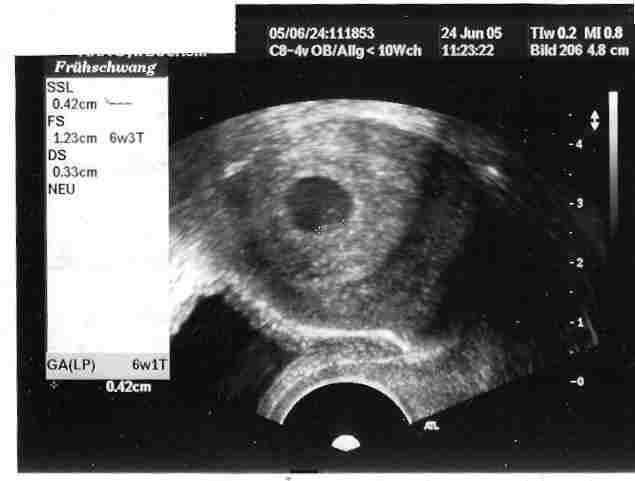

so, ich probier das jetzt mal mit dem US-Bild.... viel ist allerdings noch nicht zu sehen...

das weiße in der "ecke" ist unser zwerg. beim ersten mal 4mm groß, beim 2. mal (VU2) schon 10mm!!!